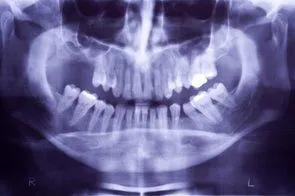

Loss of posterior teeth may result in excessive forces being placed on your remaining teeth. Fortunately, the use of dental implants and crowns allow you to replace these missing teeth. However, the position of the sinus in the upper posterior areas may be too low for proper placement of dental implants.

A simple procedure allows the sinus floor to be repositioned, creating enough space to properly place an implant. Various grafting materials are used to encourage your bone to grow more quickly into the area, helping to stabilize the dental implant. Replace with your own bone in this area the grafting material as it grows into the area.

Under certain conditions, an even simpler procedure can be utilized. When possible, the bone remaining under the sinus floor is gently “pushed up”, thus lifting the floor of the “dropped” sinus. Bone replacement materials are then placed beneath this lifted bone. Once again the bone materials are replaced as your body grow new bone into this area.